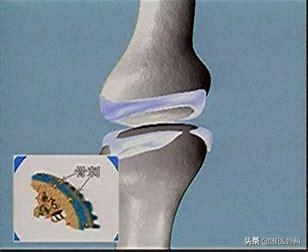

虽然,骨关节炎的疼痛表现在关节,但究其病因其实在关节表面覆盖的一层软骨。当人步入中年以后,人体各脏器开始衰老,软骨自然也不可避免地发生退化。我们对于膝关节骨关节炎其实已经比较了解了,我们就以膝关节骨关节炎为例,软骨就像是覆盖在真正的骨(胫骨、股骨、髌骨等)表面的一层保护套,软骨的性能优良,可以承担我们在日常生活中出现的膝关节磨损、冲撞、震荡等等,就好像机器运行过程中的减震垫和耐磨垫一样。而随着时间的推移,软骨的自身性能因为衰老等因素出现的降低,此外经年累月的磨损和冲击也导致软骨层越来越薄,最终出现了软骨完全磨穿,真正的骨与骨发生摩擦,由于真正的骨表面的骨膜下神经的存在,疼痛就成为了膝关节骨关节炎最为直接和明显的症状表现。